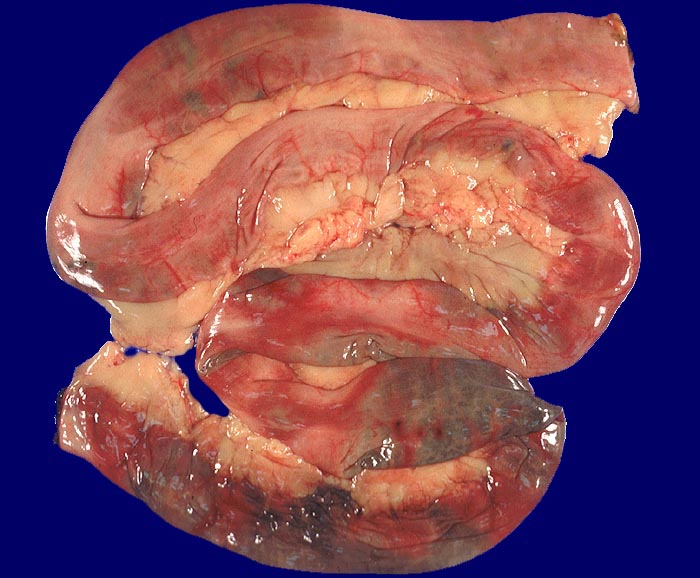

embolischer Mesenterialinfarkt

vaskulär / Durchblutungsstörung

Dünndarm

Dunkle Verfärbung der Darmschlingen und injizierte Serosa.

Alter Myokardinfarkt Parietalthrombus. Frische Emboli in eröffneten Ästen der Arteria mesenterica superior.